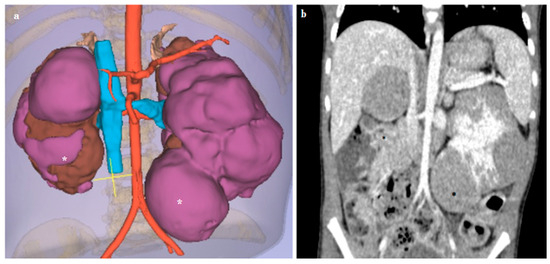

3.3. Kidney Lesions and Congenital Anomalies

| Case n. 4 | Female | 3 years | Nephroblastomatosis | Bilateral |

| Case n. 5 | Male | 3 months | Wilms’ tumor | Right |